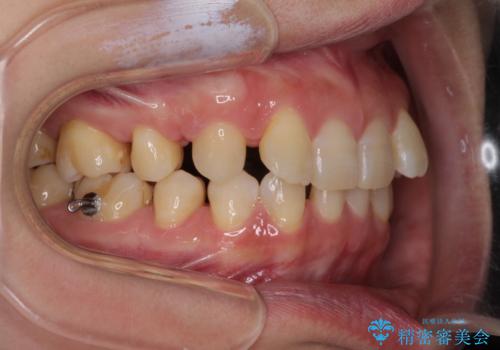

下顎2前歯の欠損 インビザラインによる抜歯矯正

- 下顎前歯欠損による歯列不正を気にして来院された患者様です。

下顎の歯列が小さく、下顎前歯が隠れてしまう過蓋咬合(ディープバイト)であったため、

マウスピースでの抜歯矯正特有の抜歯スペースに向かって奥歯が傾斜する動きが顕著に表れ、ディープバイトは改善されませんでした。

前歯のみが強く接触し、奥歯で咬めない期間も続いたため、ワイヤー装置などを補助的に使用し、何とか終了させることができました。